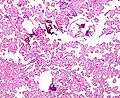

Choroid plexus papilloma, also known as papilloma of choroid plexus, is a rare benign neuroepithelial intraventricular WHO grade I lesion found in the choroid plexus.[1] It leads to increased cerebrospinal fluid production, thus causing increased intracranial pressure and hydrocephalus.[2]

The tumor is neuroectodermal in origin and similar in structure to a normal choroid plexus. They may be created by epithelial cells of the choroid plexus.